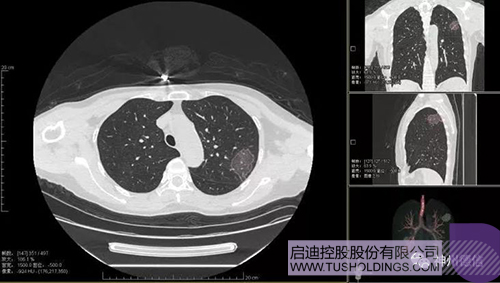

神州德信新冠肺炎檢測(cè)及智能量化分析系統(tǒng)

啟迪戰(zhàn)略投資企業(yè)神州德信作為國(guó)內(nèi)領(lǐng)先的肺部影像人工智能企業(yè),針對(duì)新型冠狀病毒肺炎開(kāi)發(fā)了智能檢測(cè)及量化分析系統(tǒng),并在陜西、重慶等地定點(diǎn)醫(yī)院投入使用。該系統(tǒng)在疑似病例大規(guī)模快速篩查及精準(zhǔn)診斷方面發(fā)揮了重要作用,特別是其具有的肺炎患者臨床影像跟蹤量化隨訪功能,為快速有效阻斷疫情擴(kuò)散提供了有力武器。